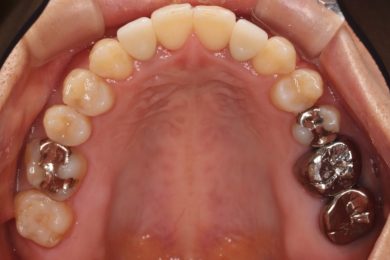

先天性欠如による上顎前歯欠損部にインビザライン術前矯正とインプラントを埋入した症例

初診時・インプラント・終了時